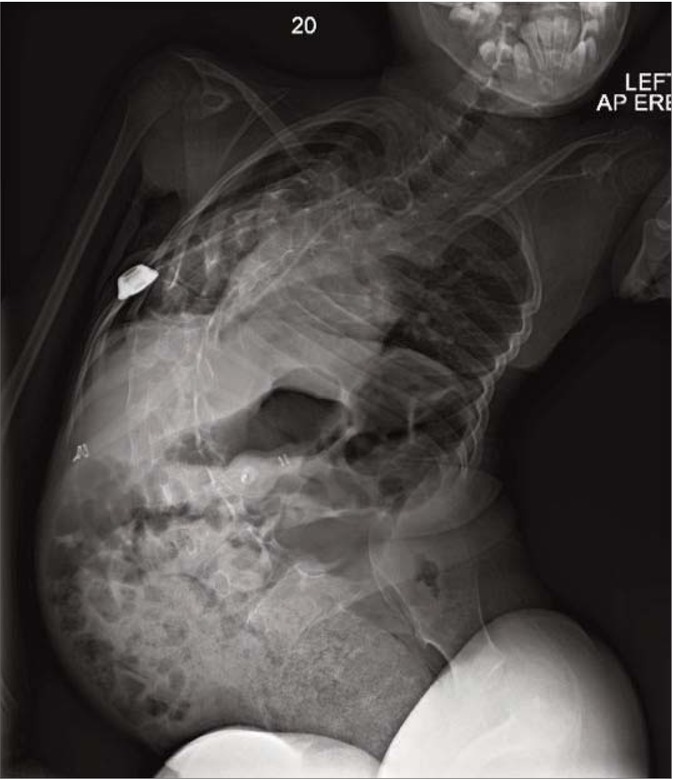

Portacath re-insertion by interventional radiologists failed. PCC prophylaxis was attempted peripherally but was complicated by journey times to and from hospital and became increasingly difficult over the following months. Limited venous access was exacerbated by positional complications of muscular dystrophy, she now had significant scoliosis (Figure 2) and elbow contractures, which made positioning for peripheral treatment virtually impossible, only the ulnar veins, were accessible. A clinical decision was made to treat her with BPL Factor X due to:

Figure 2

Complications including significant scoliosis complicated positioning for peripheral treatment